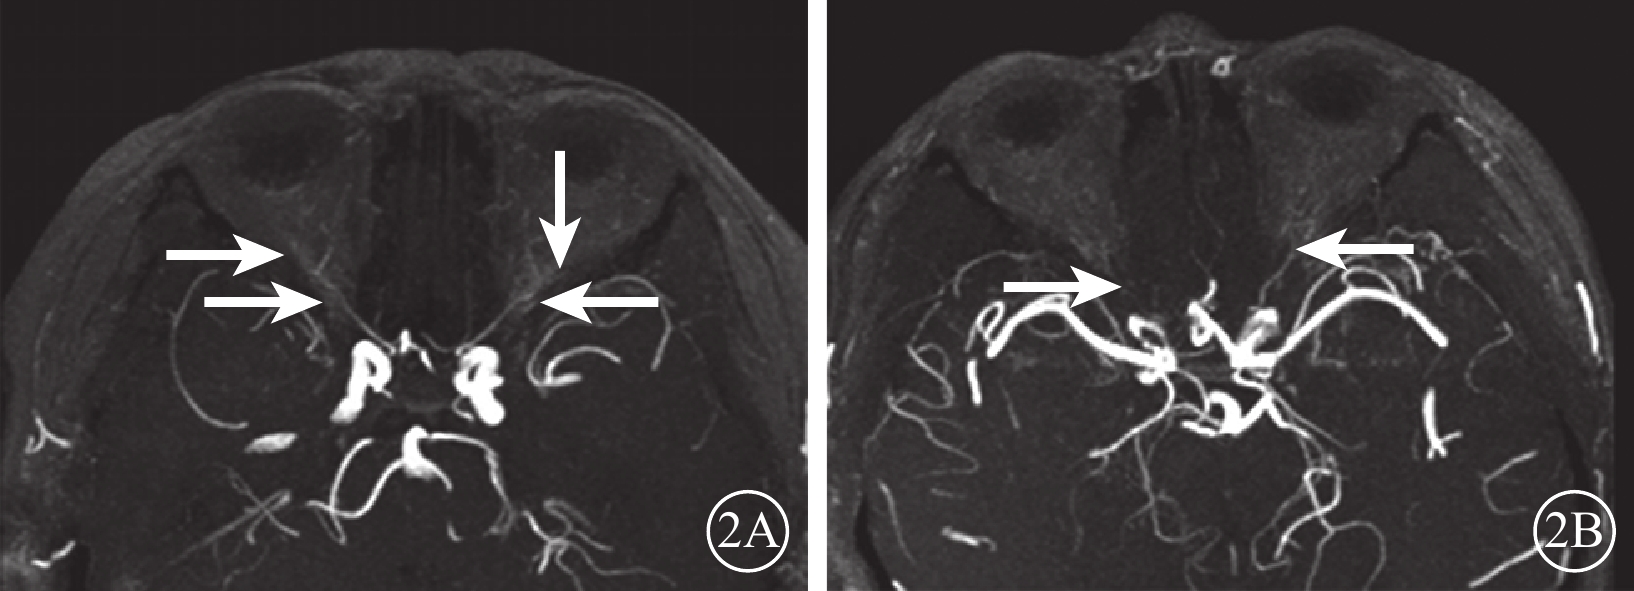

DR組72只眼中,眼動脈MRA 0級28只眼(38.9%);Ⅰ級28只眼(38.9%),其中眼動脈主干及其主要分支(鼻背動脈和淚腺動脈)顯影淺淡、外形變硬(圖2A)12只眼,眼動脈主干顯影正常、分支顯影中斷或不顯影14只眼;Ⅱ級16只眼(22.2%),其中眼動脈狹窄、僵硬伴分支顯影淺淡10只眼,分支顯影中斷或不顯影(圖2B)4只眼,眼動脈主干及其主要分支均不顯影2只眼。行CTA檢查的24只眼中,0級13只眼;Ⅰ級6只眼,其中眼動脈主干及其主要分支(鼻背動脈和淚腺動脈)顯影淺淡、管壁變硬(圖3A)4只眼,眼動脈主干顯影正常、分支不顯影2只眼;Ⅱ級5只眼,其中眼動脈主干伴分支明顯狹窄、僵硬(圖3B)3只眼,表現為眼動脈主干顯影分支不顯影2只眼。DR組眼動脈MRA、CTA分級一致性分析,Kappa值=0.86,一致性極強(表1)。DR組眼動脈MRA與對照組眼動脈MRA不同分級眼數比較,差異有統計學意義(Z=?5.74,P=0.000)。

圖2

DR患者MRA像。2A. MRAⅠ級,雙側眼動脈主干及其主要分支(鼻背動脈和淚腺動脈)顯影淺淡,走形稍僵直(白箭);2B. MRAⅡ級,右側眼動脈主干可見細線樣顯影,其分支鼻背動脈及淚腺動脈未見明確顯示,左側眼動脈主干顯影纖細淺淡,分支鼻背動脈及淚腺動脈顯示不清(白箭)

圖2

DR患者MRA像。2A. MRAⅠ級,雙側眼動脈主干及其主要分支(鼻背動脈和淚腺動脈)顯影淺淡,走形稍僵直(白箭);2B. MRAⅡ級,右側眼動脈主干可見細線樣顯影,其分支鼻背動脈及淚腺動脈未見明確顯示,左側眼動脈主干顯影纖細淺淡,分支鼻背動脈及淚腺動脈顯示不清(白箭)

DR組72只眼中,眼動脈MRA 0級28只眼(38.9%);Ⅰ級28只眼(38.9%),其中眼動脈主干及其主要分支(鼻背動脈和淚腺動脈)顯影淺淡、外形變硬(圖2A)12只眼,眼動脈主干顯影正常、分支顯影中斷或不顯影14只眼;Ⅱ級16只眼(22.2%),其中眼動脈狹窄、僵硬伴分支顯影淺淡10只眼,分支顯影中斷或不顯影(圖2B)4只眼,眼動脈主干及其主要分支均不顯影2只眼。行CTA檢查的24只眼中,0級13只眼;Ⅰ級6只眼,其中眼動脈主干及其主要分支(鼻背動脈和淚腺動脈)顯影淺淡、管壁變硬(圖3A)4只眼,眼動脈主干顯影正常、分支不顯影2只眼;Ⅱ級5只眼,其中眼動脈主干伴分支明顯狹窄、僵硬(圖3B)3只眼,表現為眼動脈主干顯影分支不顯影2只眼。DR組眼動脈MRA、CTA分級一致性分析,Kappa值=0.86,一致性極強(表1)。DR組眼動脈MRA與對照組眼動脈MRA不同分級眼數比較,差異有統計學意義(Z=?5.74,P=0.000)。

圖2

DR患者MRA像。2A. MRAⅠ級,雙側眼動脈主干及其主要分支(鼻背動脈和淚腺動脈)顯影淺淡,走形稍僵直(白箭);2B. MRAⅡ級,右側眼動脈主干可見細線樣顯影,其分支鼻背動脈及淚腺動脈未見明確顯示,左側眼動脈主干顯影纖細淺淡,分支鼻背動脈及淚腺動脈顯示不清(白箭)

圖2

DR患者MRA像。2A. MRAⅠ級,雙側眼動脈主干及其主要分支(鼻背動脈和淚腺動脈)顯影淺淡,走形稍僵直(白箭);2B. MRAⅡ級,右側眼動脈主干可見細線樣顯影,其分支鼻背動脈及淚腺動脈未見明確顯示,左側眼動脈主干顯影纖細淺淡,分支鼻背動脈及淚腺動脈顯示不清(白箭)